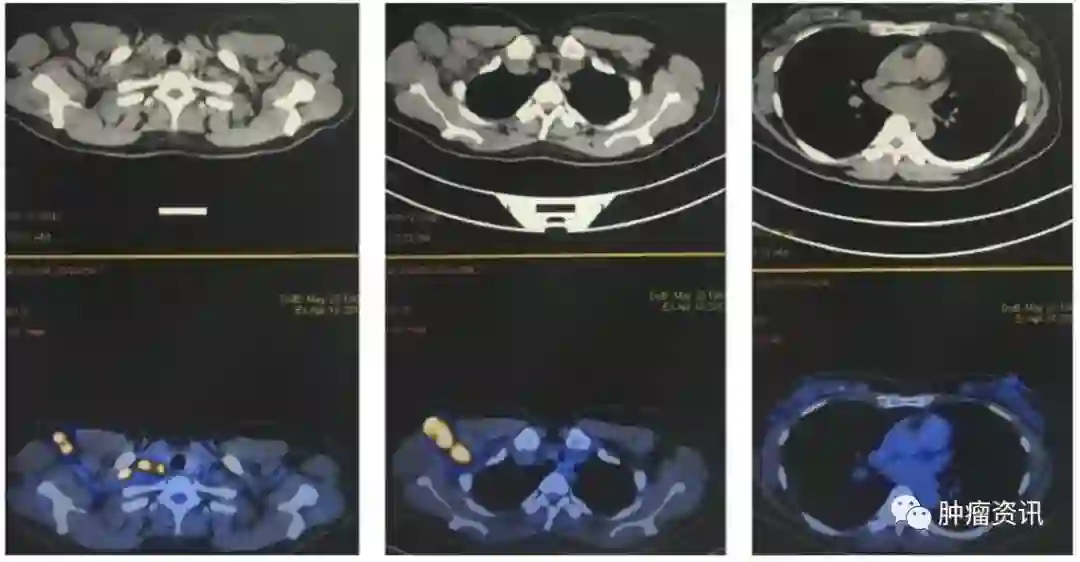

实验室检查:血肿瘤标记物:CA153 32.4U/ml,CA125 46.43 U/ml,CEA 5.92 ng/ml。乳腺MRI示(图1):右腋窝、右锁骨上肿大淋巴结,最大为38mm×38mm,强化明显,符合转移。右胸廓内动脉旁小淋巴结,9mm×8mm,强化明显,不除外转移。双乳可见直径为3~6mm多发小结节,等T1稍高T2信号,考虑为增生结节,余未见明显。颅脑MRI未见明显异常。PET-CT示(图2):右锁骨上、右腋窝多个肿大淋巴结,最大约为25mm×32mm,SUVmax为18,符合转移瘤,余未见明显异常。

图2 患者入院PET-CT

于2015年8月4日至9月21日行多西他赛联合曲妥珠单抗、帕妥珠单抗治疗3周期,治疗过程顺利。复查PET-CT提示影像学完全缓解。